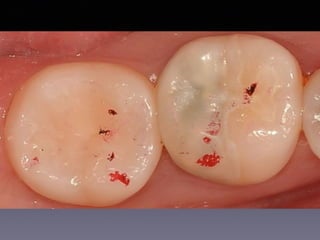

#2, #14 direct pulp capping

follow-up

(30 male)

2012 09 18

25m later